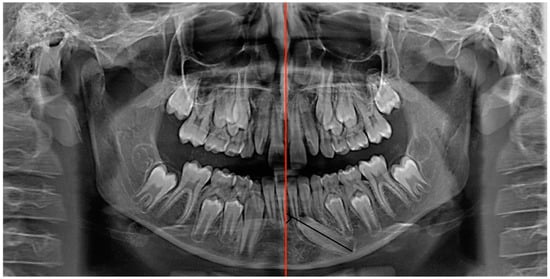

A panoramic radiograph showed that element 3.3 was deviated from its normal eruption path. The cuspid of the impacted canine was tilted mesially and positioned at the level of the right central incisor (element 3.1), close to the lower third of the root. The angle of the long axis of the canine to the line passing through the midline, traced according to Bertl et al. [4], was 60°. The deciduous element 7.3 was still present with its entire root (Figure 3).

Figure 3. Pre-treatment panoramic radiograph. The angle subtended by the line passing through the mandibular midline (red) and the line passing through the long axis of the mandibular canine (black) were traced.